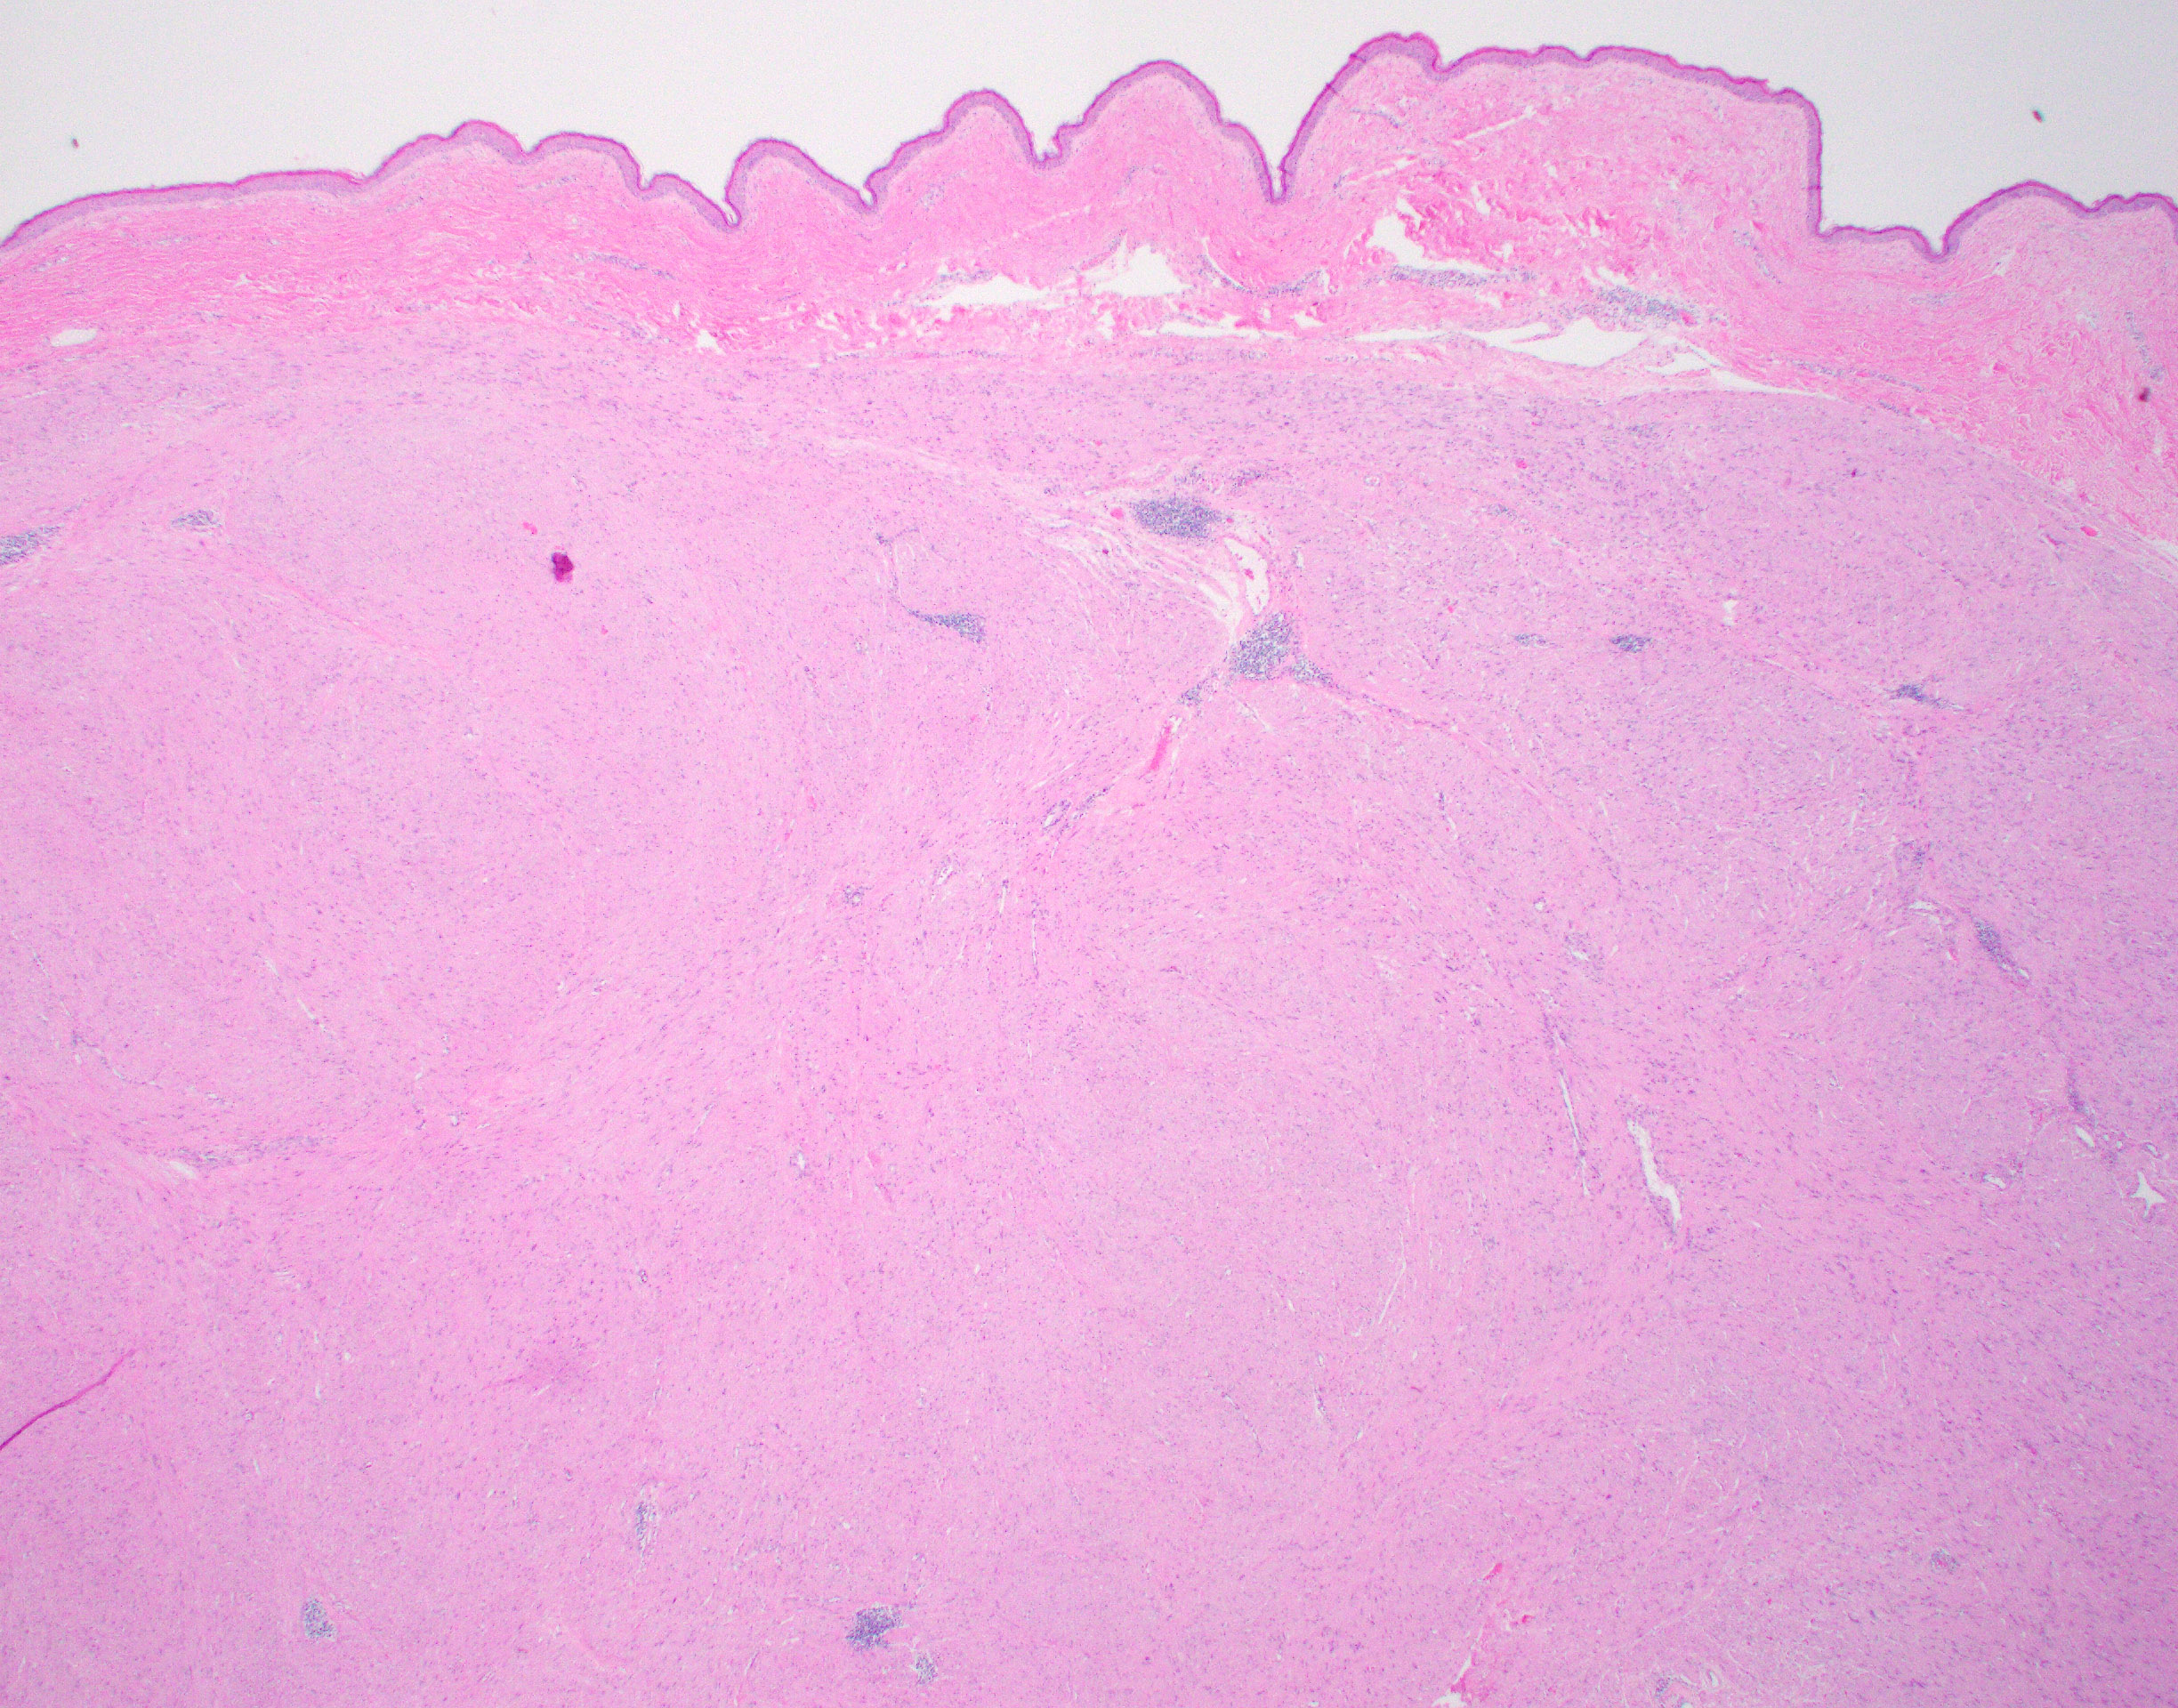

The patient is showing well-circumscribed (Fig 1) leiomyomatous lesions with features of the Hereditary Leiomyomatosis and Renal Cell Cancer (HLRCC) Syndrome (OMIM 150800, AKA Reed’s syndrome) which is produced due to germline mutations of the gene coding for the mitochondrial enzyme Fumarate Hydratase (FH, 1q43). This syndrome is characterized by multiple cutaneous, and in women uterine, leiomyomas exhibiting some distinctive features seen in this particular lesion; mainly cytoplasmic eosinophilic globules (Figure 2), nuclei with powdery chromatin exhibiting prominent nucleoli (Figure 3). Uterine examples tend to show similar albeit more pronounced nuclear features in addition to Hemangiopericytoma-like (HPC-like) vasculature, nuclear periodicity among other unique characteristics. Likewise, renal cell carcinomas arising in the context of HLRCC have their own set of distinct features including similar powdery chromatin and large nuclei with viral-like macronucleoli. These renal tumors were historically classified as type II papillary renal cell carcinomas (RCCs) or unclassifiable RCCs. The absence of the normal enzyme can be demonstrated by immunohistochemistry for Fumarate Hydratase (FH), which will show loss of staining in the lesional cells like in our case (Fig 4). In addition, one could performed immunohistochemistry for the abnormal product of the mutated FH gene (2-Succinocysteine, 2SC) a test that is not widely available.